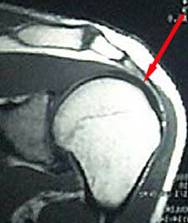

Zur Diagnose wird In der Regel mit einer Schultergelenksuntersuchung begonnen. Hier wird die Abspreizfähigkeit gegen Widerstand, die Außendrehung gegen Widerstand bei hängendem Arm und gebeugtem Ellenbogen bestimmt. Während die Abspreizfähigkeit die Funktion des Musculus supraspinatus wiederspiegelt, bestimmt man mit der Aussendrehung gegen Widerstand bei hängendem Arm und gebeugtem Ellenbogen die Funktion des Musculus teres minor und des Musculus infraspinatus. Zusätzlich stehen bildgebende Verfahren, wie beispielsweise Röntgenbildaufnahmen, Ultraschalluntersuchung der Schulter oder – als präziseste bildgebende Technik die Magnetresonanztomographie der Schulter (MRT) zur Verfügung.